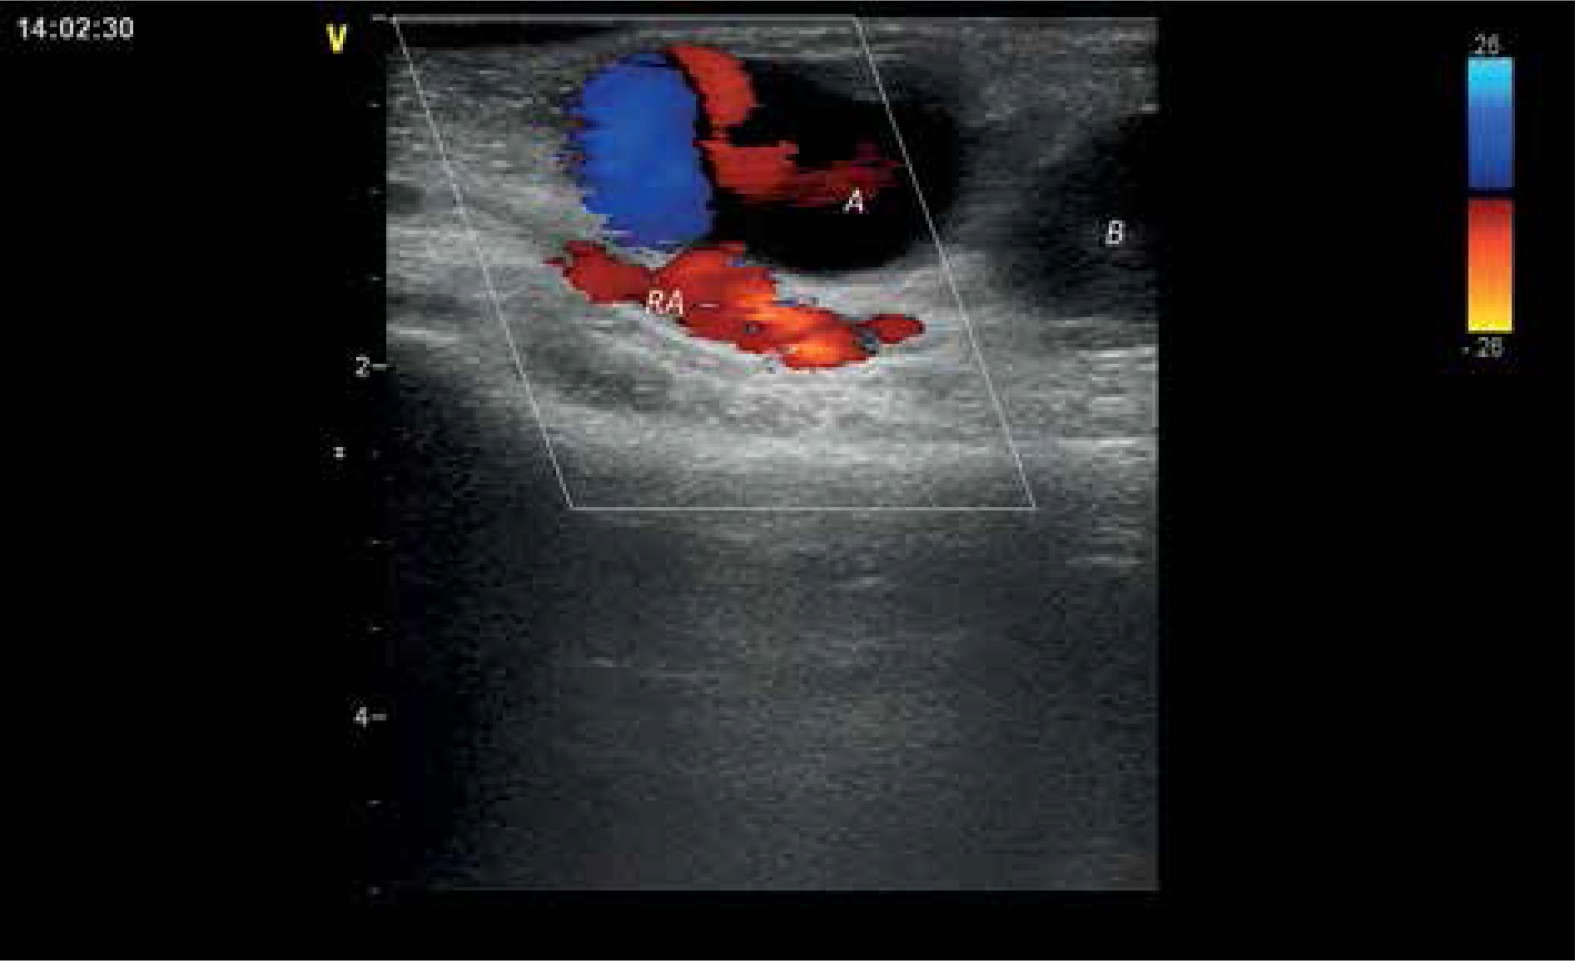

Figure 2

Pseudoaneurysm entry with blood outflow from the radial artery and patent distal part of a vessel

A – first chamber, B – second chamber, RA – radial artery.

Figure 3

Communication between the first and second chamber